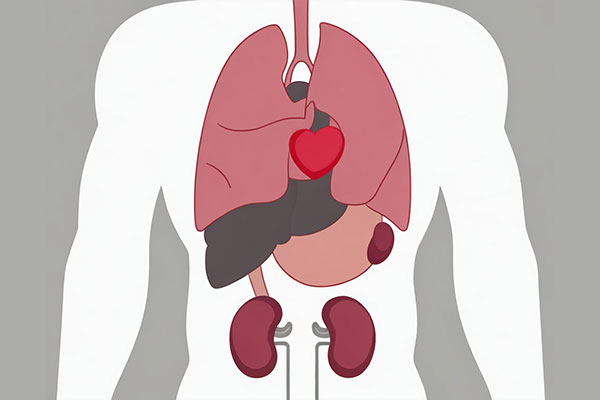

ж„ҸиҜҶдёҖдёӢиҮӘе·ұзҡ„дә”и„Ҹе…ӯи…‘пјҒ

еҗ„дәәзңҹзҡ„зҹҘи·ҜвҖңдә”и„Ҹе…ӯи…‘вҖқжҳҜжҢҮд»Җд№Ҳеҗ—пјҹJ9йӣҶеӣўеӣҪйҷ…е•ҶеӯҰйҷўдёәжӮЁи§Јзӯ”пјҒ